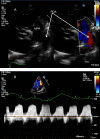

This review article will guide the reader through the basics of echocardiographic assessment of congenital left to right shunts in both paediatric and adult age groups. After reading this article, the reader will understand the pathology and clinical presentation of atrial septal defects (ASDs), ventricular septal defects (VSDs), atrioventricular septal defects (AVSDs) and patent arterial duct. Echocardiography is the mainstay in diagnosis and follow-up assessment of patients with congenital heart disease. This article will therefore describe the echocardiographic appearances of each lesion, and point the reader towards specific features to look for echocardiographically.